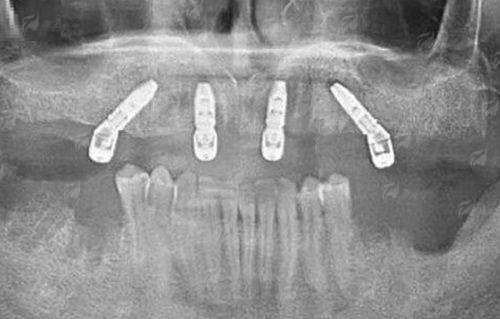

1. 牙齿种植修复系列:开展单颗、多颗及半口/全口种植。技术亮点在于采用数字化导板辅助种植技术,通过术前CBCT数据采集、三维重建模拟,实现种植体的精细植入,有效规避神经血管,提升手术安心性与长期稳定性。成效特点是咀嚼功能修复良好,美学仿真度高。适用于单牙缺失、多牙缺失及牙列缺损,且牙槽骨条件允许的成年患者。